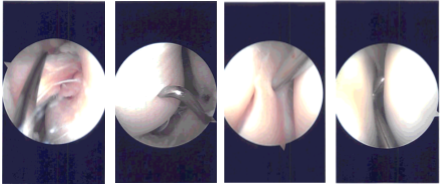

Examination of the medial compartment showed frayed tearing of the anterior horn of the medial meniscus. Shaver was used to clean up the meniscus. Balanced margins were achieved. There was no tear of the body of the posterior horn. The root was intact.

Medial femoral condyle showed grade 1 to grade 2 osteochondral lesion, which was cleaned up with a shaver. Examination of the intercondylar notch showed intact ACL. Examination of the lateral compartment showed intact lateral meniscus as well as intact cartilage of the lateral tibiofemoral compartment.

Examination of the patellofemoral compartment showed no lesion of the patellofemoral cartilage. Patellar tracking was proper. Examination of medial and lateral gutters showed no loose body. The scope was inserted from the medial condyle and the findings were reconfirmed. Final pictures were taken and saved.

Intraoperative Arthroscopy Images